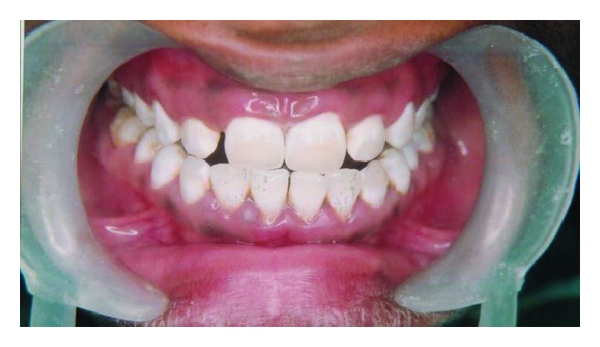

A thirty-year-old male came to the dental hospital with chief complaint of dark brown staining of the anterior teeth. He also wanted a least invasive, cost-effective treatment to enhance his esthetics. From the appearance of his teeth, diagnosis of moderate flourosis staining was determined by Dean’s Fluorosis Index (Table 1). The most significant staining occurring on the maxillary anterior teeth contained dark brown streaks in the middle third of the facial surfaces (Figure 4). The same procedure for the microabrasion was repeated as was done in Section 2. After the procedure was completed, fluoride gel application was placed on the teeth to reduce the postoperative sensitivity. The rubber dam was removed for the evaluation of the result by the patient (Figure 5). The patient was quite satisfied with the results. In the above mentioned cases, patients were asked not to smoke, eat, or drink anything that could possibly stain the teeth for 24–48 hours after the treatment.